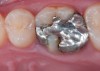

CL-IIIb high-strength 100% crystalline ceramics initially were alumina-based materials (Procera®, Nobel Biocare, nobelbiocare.com), and more recently zirconia-based materials (eg. LAVA™, 3M ESPE, 3mespe.com; Prettau®, Zirkonzahn, zirkonzahn.com). Alumina systems have proven successful for single units, but are being replaced by zirconia and lithium disilicate due to the increased risk of failure in the molar region.24,25 Zirconia can also be used when significant tooth structure is missing, when high risk for flexure and stress is present, for posterior full-crown and fixed partial denture situations (Figure 13 and Figure 14), and when adhesive bonding is problematic, such as with subgingival margins.

In cases where the bond and seal cannot be maintained (ie, high-risk bonding situations, including moisture control problems, high shear and tensile stresses on bonded interfaces, and variable bonding interfaces), high-strength CL-III ceramics or metal ceramics (CL-IV, see below) are appropriate, because they can be placed using conventional cementation techniques. A concern with full-contour zirconia, however, is wear on opposing dentition.26

Whether alumina or zirconia, these materials demonstrate greater strength than CL-I and CL-II materials and can be used to fabricate a core substructure to replace metal. However, they are more opaque due to their greater crystalline content, which detracts from overall esthetics. They are therefore layered with porcelain,27 allowing these materials to offer both superior strength and improved esthetic results.28 CL-III high-strength ceramics require a thickness of 1.2 mm to 1.5 mm, depending on the substrate color.20,25 More translucent versions are now used in the posterior region as full-contour or monolithic all-zirconia restorations. Marketed first in this category was BruxZir® (Glidewell Laboratories, bruxzir.com), with many other manufacturers entering the market (Figure 15 and Figure 16).

Fig 13. Porcelain-layered zirconia framework (CL-IIIb) with layered pink porcelain for the gingiva (Fig 13); final image in the mouth of the porcelain-layered zirconia framework (Fig 14) (images courtesy of Aram Torosian, MDC).

Figure 13

Fig 14. Porcelain-layered zirconia framework (CL-IIIb) with layered pink porcelain for the gingiva (Fig 13); final image in the mouth of the porcelain-layered zirconia framework (Fig 14) (images courtesy of Aram Torosian, MDC).

Figure 14

Fig 17. Two-molar full-crown porcelain-fused-to-metal restoration made with a CL-IV substrate

Figure 17